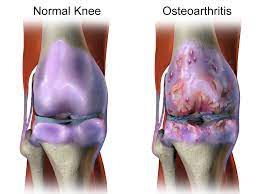

관절염 치료법

① 보존적인 치료법

- 항염증 약물, 운동 요법 등으로 진행

- 초기 퇴행성 관절염 환자에게 적합

- 근력 및 근육량 키워서 유지

- 통증 줄이고, 일상적인 활동 가능하도록 개선

② 수술적 치료법

- 관절 연골이 많이 닳고 손상이 심한 환자에게 적용

- 인공관절 수술, 교정 절골술, 관절 내시경 등이 있음

- 보존적 치료에도 불구하고 통증‧기능장애가 계속 악화하면 고려

- 불필요한 관절경 치료는 효과 거의 없고, 부작용 위험 증가

③약물 치료

- 진통 억제 및 항염증제재를 사용하여 관절염으로 인한 통증을 없애고 관절 기능 유지하기 위함

- 이 약들이 퇴행성 관절염을 완치시킬 수 없으나 통증 경감에 효과가 있고, 이로 인해 일상생활이 가능

- 심한 통증이 있는 경우 흔히 ‘뼈주사'라고 불리는 스테로이드 제재를 관절 내에 주입하는 경우가 있으며, 증상의 호전에는 효과가 있음

- 장기적으로 보면 연골의 변성을 촉진시켜 해로운 영향을 끼친다.